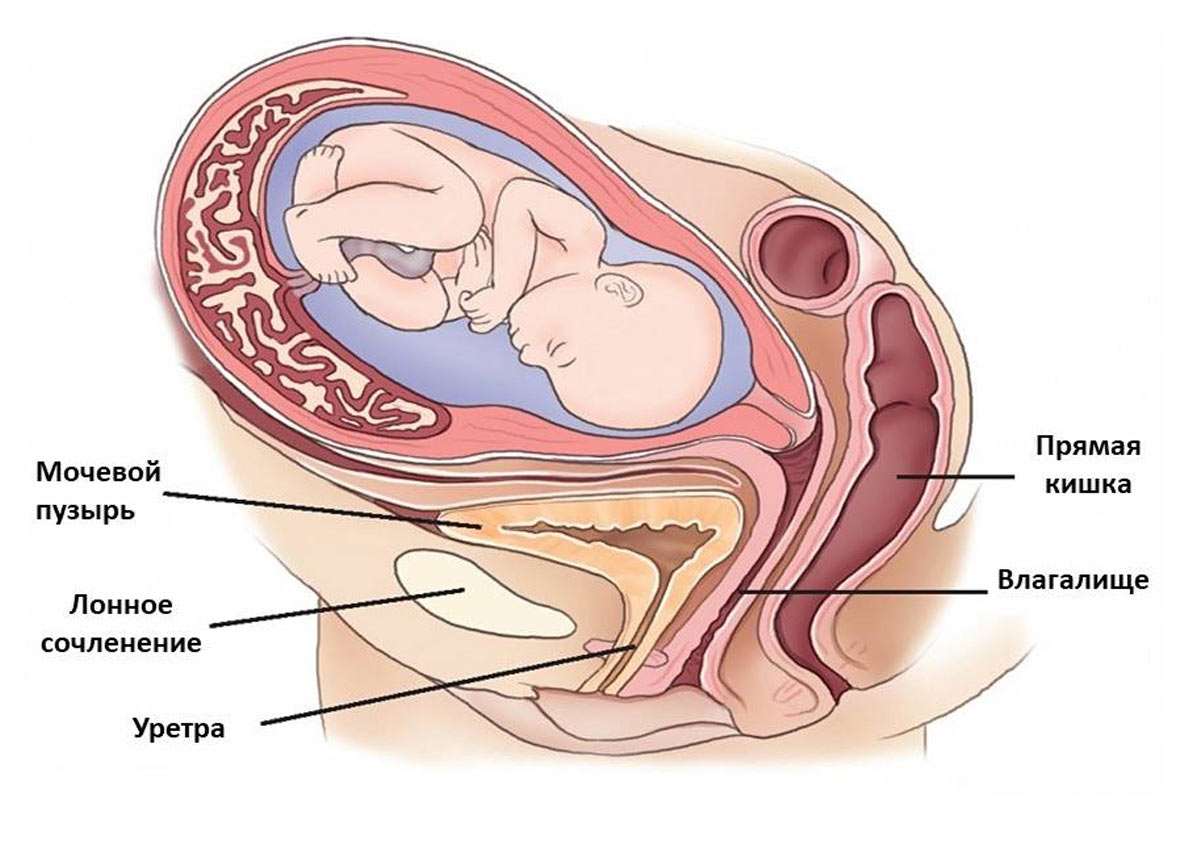

Физиология беременности: строение органов

Раздел: Моменты озарения